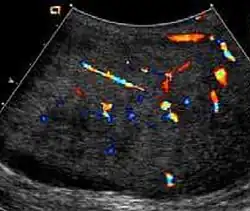

Rhabdomyosarcoma (a) Longitudinal section (composite image) of high resolution ultrasound of a 14-year-old boy shows a well defined hypoechoic extratesticular mass is found in the left scrotum, hydrocele is also present. (b) Color Doppler ultrasound shows that the mass is hypervascular.

Rhabdomyosarcoma is the most common tumor of the lower genitourinary tract in children in the first two decades, it may develop anywhere in the body, and 4% occur in the paratesticular region which carries a better outcome than lesions elsewhere in the genitourinary tract. Clinically, the patient usually presents with non-specific complaints of a unilateral, painless intrascrotal swelling not associated with fever.

Transillumination test is positive when a hydrocele is present, often resulting in a misdiagnosis of epididymitis, which is more commonly associated with hydrocele. The ultrasound findings of paratesticular rhabdomyosarcoma are variable. It usually presents as an echo-poor mass [Fig. 11a] with or without hydrocele. With color Doppler sonography these tumors are generally hypervascular.